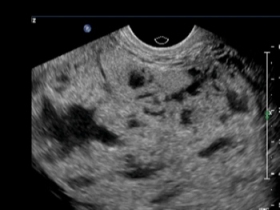

What best describes this image?

CorrectIncorrect -